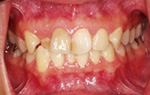

Aさんの口腔内写真です↑

吉本歯科医院では、院長の診断により、まず親知らずを抜いて全体の噛み合わせ(咬み合わせ)のバランスを

診ます。その後、矯正治療か、マウスピース治療が必要であると考えます。